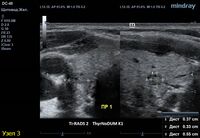

3) Узел правой доли, не прорастает капсулу щитовидной железы (0 баллов), больше широкий чем высокий (0 баллов), не имеет кальцинатов (0 баллов), с ровным четким контуром (0 баллов), изоэхогенный (1 балл), смешанной структуры (1 балл). Количество баллов 2, ACRTi-RADS2, ThyrNoDUMК1. Пункция не показана в связи с низким риском.